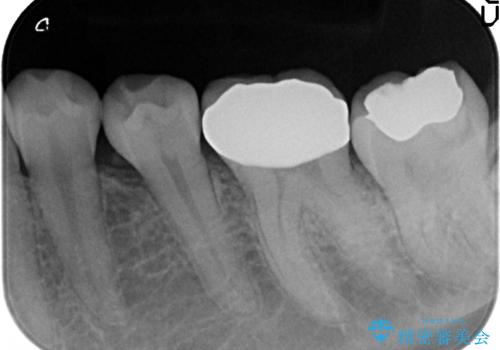

- 左下6の咬耗により歯がしみるている方の症例です。

オールセラミッククラウンによる補綴を行い、症状はなくなりました。

今回用いたオールセラミッククラウンは、ジルコニアフレームという白い素材の上にセラミックを盛っているため審美性が非常に高いのが特徴です。

またジルコニアは人工ダイヤモンドの材料にも使われているほど高い強度を持っており、そのためオールセラミッククラウンは審美性だけでなく、奥歯やブリッジの補綴も可能とするクラウンです。